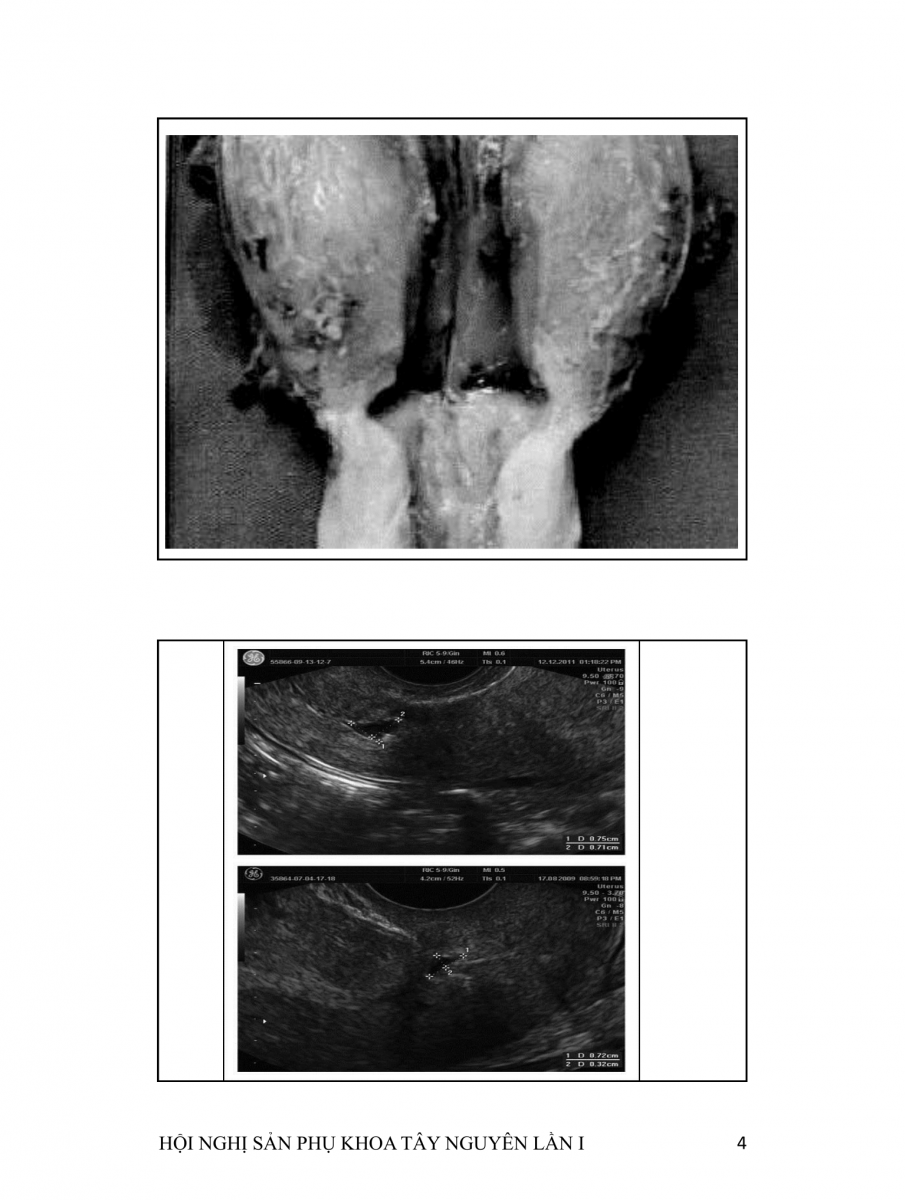

Hở khuyết sẹo mổ lấy thai  (CESAREAN SCAR DEFECTS)